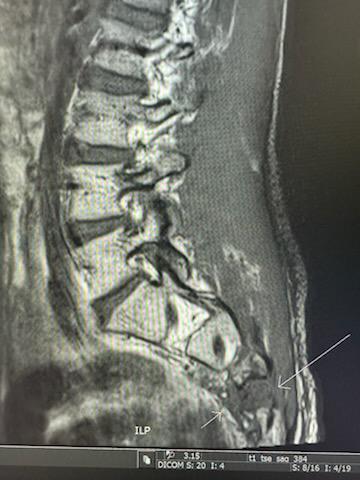

We were on ward on the 28/11/23 for an MRI which came back with good news…the tumour had not grown past the 6cm from scans done in September 2023 and that there had been no newly developed cancer … fast forward a little to the 12th of December where we noticed a small lump on Eche’s back which was close to the last protruding tumour but closer to the centre of his spine than the last. We had a repeat MRI on ward on the 14/12/23 which showed a tumour growing on his tail bone area which was growing rapidly. Drs have estimated it is growing at least a cms per week and could pick up the pace or worse keep spreading. With chemo out of the question by Eches choice and the Drs suggestion our boy will received one round of radiation on to try and relieve his pain and the pressure on his nerves to hopefully help keep mobility and quality of life going for a little longer.